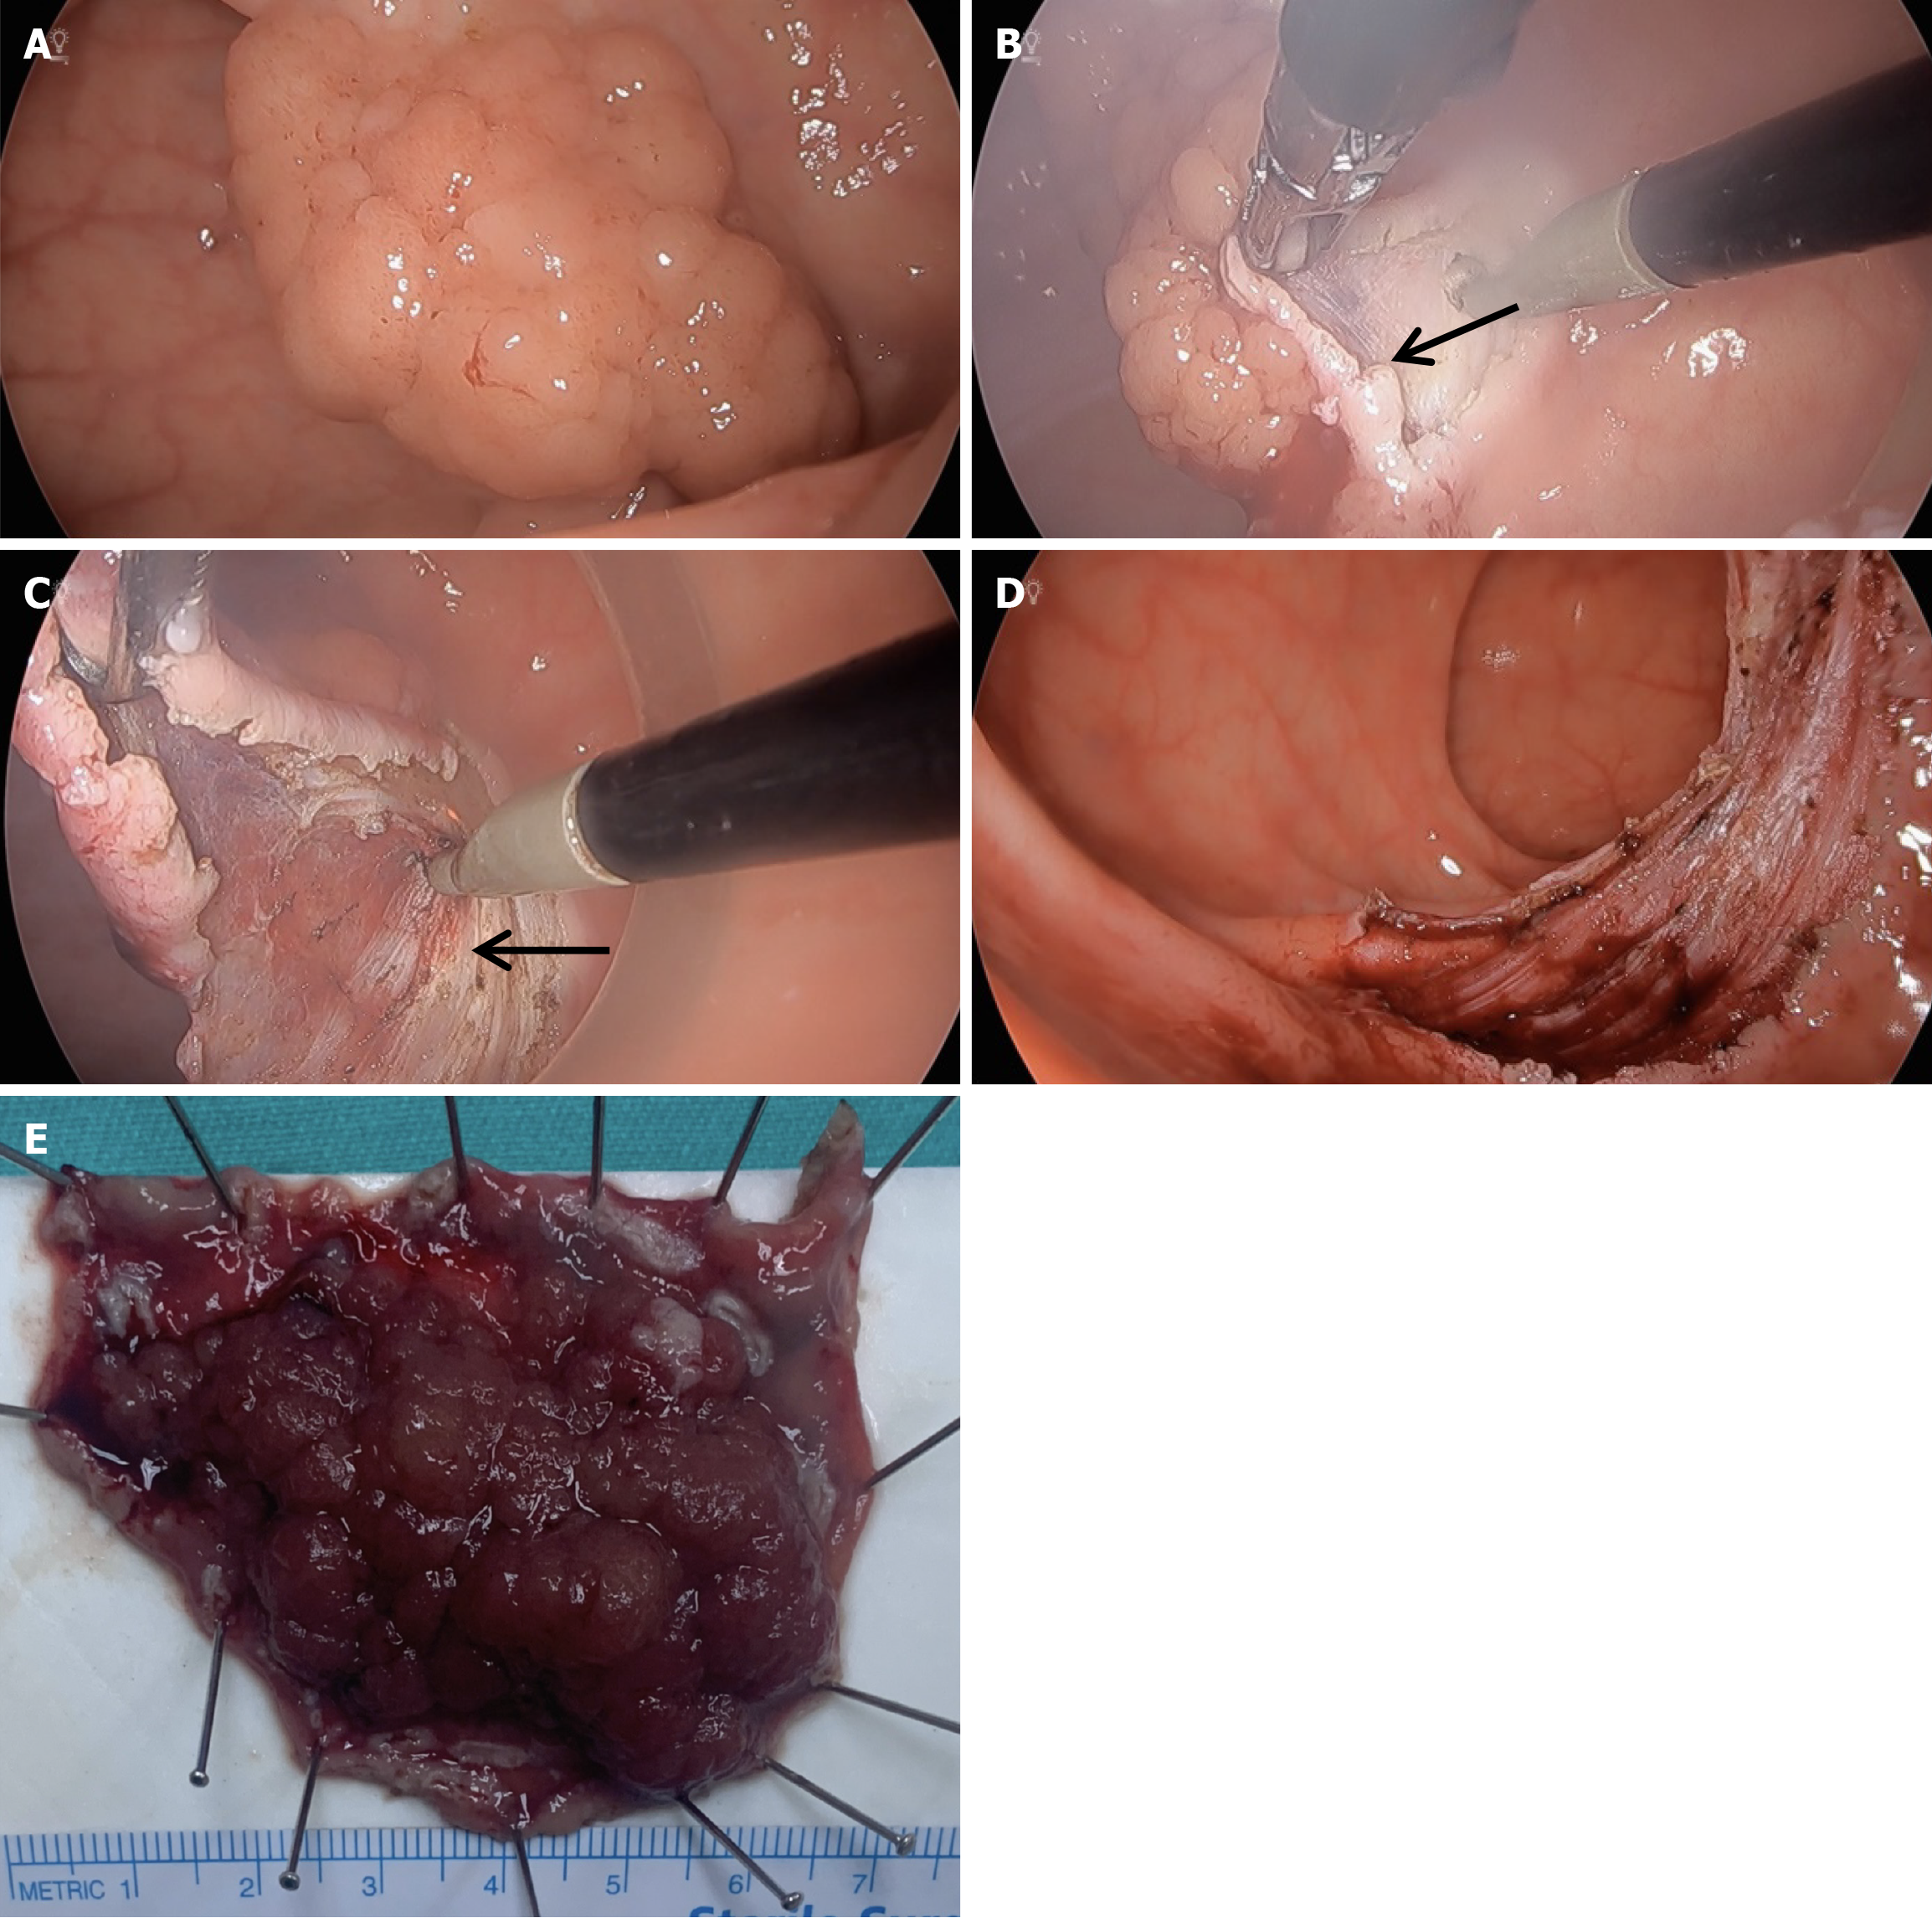

ESD is a technique that enables the removal of lesions limited to the submucosa in one piece using specialized cutting devices. The procedure consists of several stages: (1) First, the lesion to be dissected must be determined chromoendoscopically; (2) Following the marking of the determined border, an appropriate fluid injection must be made into the submucosa; and (3) The next stage is the dissection of the submucosa under the tumor after combining the area surrounding the marked borders with a preliminary incision (Figure 1)[11,12].

Figure 1

Figure 1 Sequential steps of endoscopic submucosal dissection for an early-stage colorectal lesion. A: Submucosal injection is performed to lift the lesion from the muscularis propria; B: Circumferential mucosal incision is initiated around the lesion; C: Submucosal dissection is carried out using an endoscopic knife; D: Hemostasis is achieved with coagulation forceps; E: Resected early-stage colorectal lesion after complete submucosal dissection.